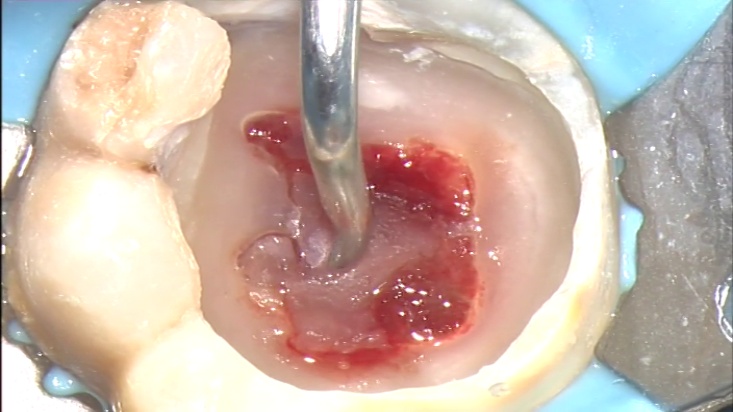

Сл. 8.29 б) Клинички изглед на коронката, по отстранување на кариесот. Преку експонираното пулпно ткиво лебди еден мал остров од дентин.